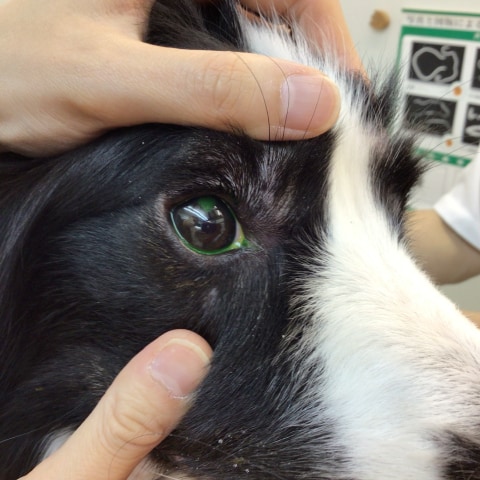

Before:下瞼が内反し毛が角膜に触れてしまっています

After:(術後1週間)下瞼が外反し毛が外側へ生えるようになり眼球への刺激が無くなりました

涙が多く来院し、下瞼が内反(眼球の方向に入り込んでしまっている)を認めました。内反することで常に毛が角膜に触れ刺激により涙が出てしまっている状態でした。

下眼瞼内反は形体異常のため外科手術にて瞼が内側に入り込んでしまっている部分を切開、縫合する眼瞼形成術を実施させて頂きました。

眼瞼内反による毛の角膜刺激は目の違和感や痛みを伴い、悪化すると結膜炎や角膜潰瘍(角膜に傷がついてしまう)を引き起こし更に痛みを引き起こしてしまうことがあります。軽度な場合には点眼薬を用いた内科療法もご提案させていただきますのでベストな治療を一緒に決めさせてください。涙が多い、涙やけがある、目が開きづらいなどありましたらご気軽にご相談くださいね。